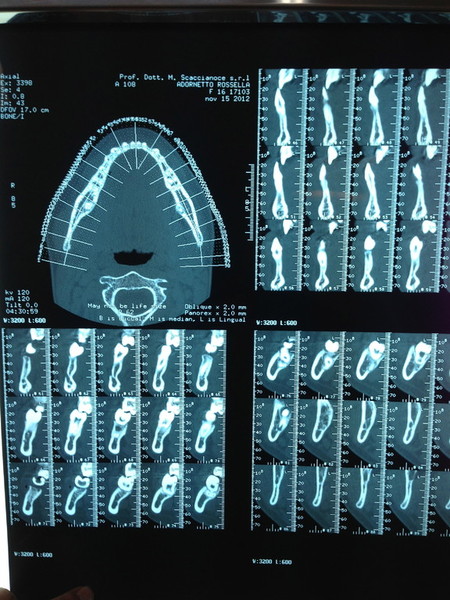

Paziente candidato a intervento di chirurgia Ortognatica